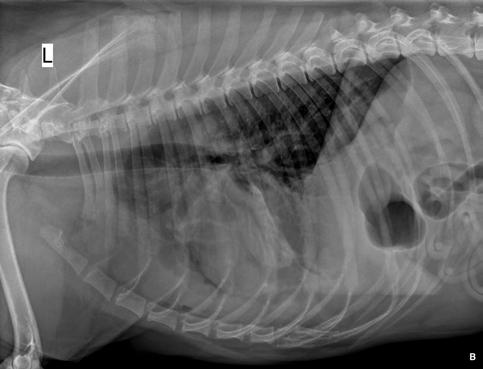

Se realiza radiografía de tórax (Fig. 1) que revela car-

diomegalia generalizada severa, índice de Buchanan de 15 cuerpos vertebrales, que puede corresponder a un severo aumento de las cámaras cardiacas, o a la presencia de líquido pericárdico. Se observa, además, un patrón pulmonar intersticial perihiliar, compatible con edema pulmonar, foco de neumonía o hemorragia pulmonar.

M. López,1 V. Fernández,2 J. Engel3 1Servicio de cardiología y diagnóstico por imagen. 2Servicio de cirugía. Laclinicaveterinaria. c/Marroquina 26. 28030 Madrid. 3Servicio de cardiología. ANICURA-Benipeixcar Hospital Veterinario. Avinguda de la Constitució 68, bajo izq. 46009 Valencia. ANICURA-San Francisco Hospital Veterinario. c/ Sant Francesc 65. 12500 Vinaròs (Castelló). ANICURA-San Vicente Hospital Veterinario. c/ Veterinario Manuel Isidro Rodríguez García 17. 03690 San Vicente del Raspeig (Alicante). Figura 1. Radiografía lateral de tórax en la que se observa cardiomegalia generalizada, VHS 15. Patrón alveolar intersticial compatible con edema pulmonar. Patrón vascular mixto y patrón bronquial en lóbulos caudales, compatible con bronquitis crónica, mineralización por degeneración senil.

En el caso que presentamos podemos confirmar cardiomegalia severa y edema pulmonar dado que el estudio radiológico del tórax permite establecer el tamaño cardiaco y valorar el patrón pulmonar. La insuficiencia cardíaca congestiva izquierda se caracteriza por un patrón intersticial, que puede evolucionar a patrón alveolar en la región perihiliar que tiende a distribuirse hacia caudodorsal, característico del edema pulmonar cardiogénico, patrón vascular venoso.